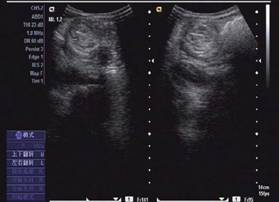

圖示:該患兒當(dāng)時(shí)聲像圖表現(xiàn)

超聲圖像表現(xiàn)

1、腸套疊部位顯示邊界清楚的包塊。其橫斷面呈大環(huán)套小環(huán)的特征性表現(xiàn),即“同心圓征”或“靶環(huán)征”。外圓呈均勻的低回聲環(huán)帶,系鞘部腸壁回聲,低回聲帶系水腫增厚的反折壁及其與鞘部之間的少量腸內(nèi)液體形成。在大的外圓內(nèi),又有一個(gè)小低回聲環(huán)帶,形成內(nèi)圓。內(nèi)、外圓間為高回聲環(huán),中心部為高回聲團(tuán),其邊緣欠光整。套疊部的縱斷面呈“套筒征”或“假腎征”。有時(shí)可能顯示套疊的頂部和頸部,頂部呈指頭狀盲端。“假腎征”通常是在套疊時(shí)間較長(zhǎng),腸壁發(fā)生嚴(yán)重水腫時(shí)出現(xiàn),或是成人患者存在腸管腫瘤或息肉時(shí)出現(xiàn)。